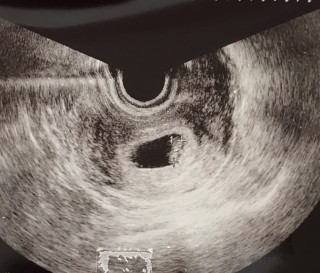

写真:7w0d:まりぽんさん

7w0d

胎芽

A9.6mm

B7.9mm

前回6w0d

A3.5mm

B2.9mm